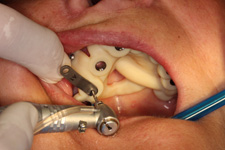

7) Operace pomocí šablony

6) Operace pomocí DENACAM